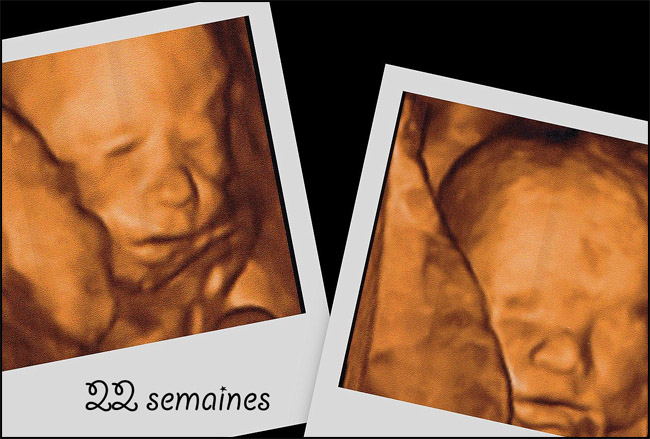

Peu avant ses quatre ans, nous découvrons dans des reportages et études américaines une approche biologique de l’autisme. C’est une révélation : à deux mois de grossesse, j’ai souffert pendant deux mois de fortes fièvres. J’ai été sous antibiotiques, ce qui a permis à Gabrielle de survivre. Ces fameux antibiotiques qui ont certainement eu des répercussions sur la flore intestinale du bébé et son système nerveux, développant un risque d’autisme sur un terrain génétiquement favorable. Les probiotiques, en rééquilibrant la flore intestinale, auraient d’excellentes répercussion neurologiques.